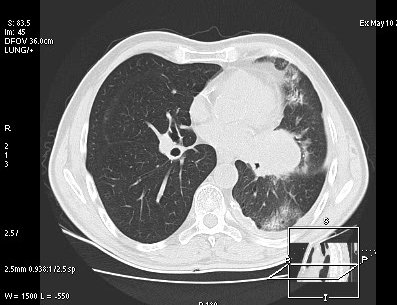

Foto: Aleksandar Ivković Foto: Aleksandar Ivković Foto: Aleksandar Ivković Strašna razlika kod pluća pušača i kovid pozitivne osobe autor: Božica Luković Zdravlje 23. jan. 2021. 12:06 > 23. jan. 2021. 12:15 0 Podeli vest: Radiolog Aleksandar Ivković od početka pandemije daje korisne informacije o svim aspektima kovida 19. On je nedavno uporedio rendgen snimke pluća zdrave osobe, pušača, osobe koja je zaražena gripom H1N1, a onda i osobe koja ima kovid 19. Razlike su zapanjujuće. Podeli vest: Oglas Objavu doktora Ivkovića sa njegovog bloga "Ljudi i ostale laži" prenosimo u celosti."Nedavno sam video u medijima da je neko preneo rdg sliku i razlike kod nalaza zdrave osobe, pušača i bolesnog od kovida 19. Kako nisam baš previše zadovoljan onim što je prikazano, evo kako to izgleda u našoj varijanti. Zdrava osoba CT nalaz kod zdrave osobe podrazumeva da ne postoje nikakvi poremećaji strukture plućnog parenhima, da su krvni sudovi uredni i da nema suženja disajnih puteva, kao i da nema uvećanih limfnih žlezda u hilusima pluća i medijastinumu. Foto: Aleksandar Ivković | Foto: Aleksandar Ivković * Foto: Aleksandar Ivković | Foto: Aleksandar Ivković Zdrava muška osoba mesec dana nakon zapaljenja pluća tokom kovida 19. Nalaz bez nekih posebnih problema iako se naziru tragovi zapaljenja. Snimak u boji je zdrava osoba, nepušač, bez ikakvih bolesti pluća u istoriji. Grip H1N1 Pokazaću samo drastične nalaze kod gripa H1N1, to je znači onaj grip koji je izazvao epidemiju španske groznice i epidemiju 2009. godine koja još uvek nije prestala (svake godine imamo makar 15%). Foto: Aleksandar Ivković | Foto: Aleksandar Ivković * Foto: Aleksandar Ivković | Foto: Aleksandar Ivković * Foto: Aleksandar Ivković | Foto: Aleksandar Ivković * Foto: Aleksandar Ivković | Foto: Aleksandar Ivković Nisu svi pacijenti imali ovakve nalaze, pokazujem one koji su imali tešku kliničku sliku. Kod gripa se sve odvija obično u sedam dana. Kao što se vidi, zapaljenje je bilo jednostrano, uglavnom. Ali kada je dolazilo do pogoršanja, onda je centralno obostrano dolazilo do edema pluća. Pušenje Kod pušača postoje razne varijante nalaza na plućima. U principu nisu tako dramatične kao što su zapaljenja. Nalaz na plućima kod pušača može biti potpuno normalan. Ovo ne pišem zato što podržavam pušenje, naprotiv, veliki sam protivnik, ali iznošenje laži nikada nije dobro. Dve dijagnoze su bitne kao posledica pušenja. Prva je hronična plućna opstruktivna bolest: Foto: Aleksandar Ivković | Foto: Aleksandar Ivković * Foto: Aleksandar Ivković | Foto: Aleksandar Ivković * Foto: Aleksandar Ivković | Foto: Aleksandar Ivković Jasna je razlika u nalazu, posebno na ovim slikama u boji, gde su ta plava polja delovi pluća koji su propali zbog cigareta (može da se uporedi sa zdravim plućima iznad).Druga bolest koja je česta kod pušača je u svakom slučaju karcinom. Foto: Aleksandar Ivković | Foto: Aleksandar Ivković * Foto: Aleksandar Ivković | Foto: Aleksandar Ivković * Foto: Aleksandar Ivković | Foto: Aleksandar Ivković * Foto: Aleksandar Ivković | Foto: Aleksandar Ivković Tkivo koje raste unutar pluća i razjeda ga. Takav je nalaz kod karcinoma pluća. Često je uzrok upotreba cigareta. Kovid 19 O kovidu sam pisao puno puta. Evo nekih slika, radi poređenja. Foto: Aleksandar Ivković | Foto: Aleksandar Ivković * Foto: Aleksandar Ivković | Foto: Aleksandar Ivković * Foto: Aleksandar Ivković | Foto: Aleksandar Ivković * Foto: Aleksandar Ivković | Foto: Aleksandar Ivković Nakon što pacijent bude izlečen od gripa ili kovida 19, pluća se mogu vratiti u normalu.To je razlika u odnosu na posledice upotrebe cigareta. Ovi snimci nisu postavljeni da bi se poredile bolesti, već da bi se ukazalo kako različite bolesti deluju na pluća. I ono što je veoma važno, ako neko dobije jednu od ovih bolesti, ne znači da u toku života neće dobiti drugu.Ne pišem zato smo smatram da sam najpametniji ili najpozvaniji da objašnjavam, nisam kao neki pojedinci ubeđen da samo ja imam znanje i istinu, pišem jer drugi ćute. Pišem jer ima i puno onih koji iznose laži, mora se tome stati na put.A ovi, koji pišu da sam umro, da sam oboleo od karcinoma, ovi koji mi žele da nađem dobro grobno mesto, šta da vam kažem, vi ste mi inspiracija. Svesni ste da sam u pravu i odlično znam da ste već uradili sve da se vakcinišete i mnogi od vas će to uraditi pre mene ali i dalje ćete ubeđivati druge da se ne vakcinišu i da je dobro za njih da se razbole i umru. Ima puno reči za vas u svim našim slovenskim jezicima, znate vi sami šta ste", piše dr Ivković.***Bonus video:https://youtu.be/MWucTT0qBsIPratite nas i na društvenim mrežama:FacebookTwitterInstagram Dr Lukić otkrio spisak svih antibiotika za kovid upalu pluća Zdravlje 0 Dr Žujović: Kako oporaviti pluća posle korone Zdravlje 0 Pet znakova da ti je kovid zahvatio pluća Zdravlje 0 Virusolog Ana Banko ruši veliku zabludu o ruskoj vakcini Emisije 0 aleksandar ivković korona kovid pluća snimak pluća Pratite nas na društvenim mrežama: Koje je tvoje mišljenje o ovoj temi? Učestvuj u diskusiji ili pročitaj komentare Budite prvi koji će ostaviti komentar Pošalji komentar Pročitaj komentare (0)